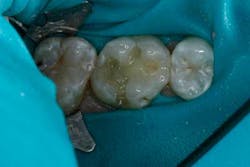

The occlusion was checked and adjustments were completed (Figs. 14 through 16). After the final polish was accomplished, the restoration was completed (Figs. 17 through 19).